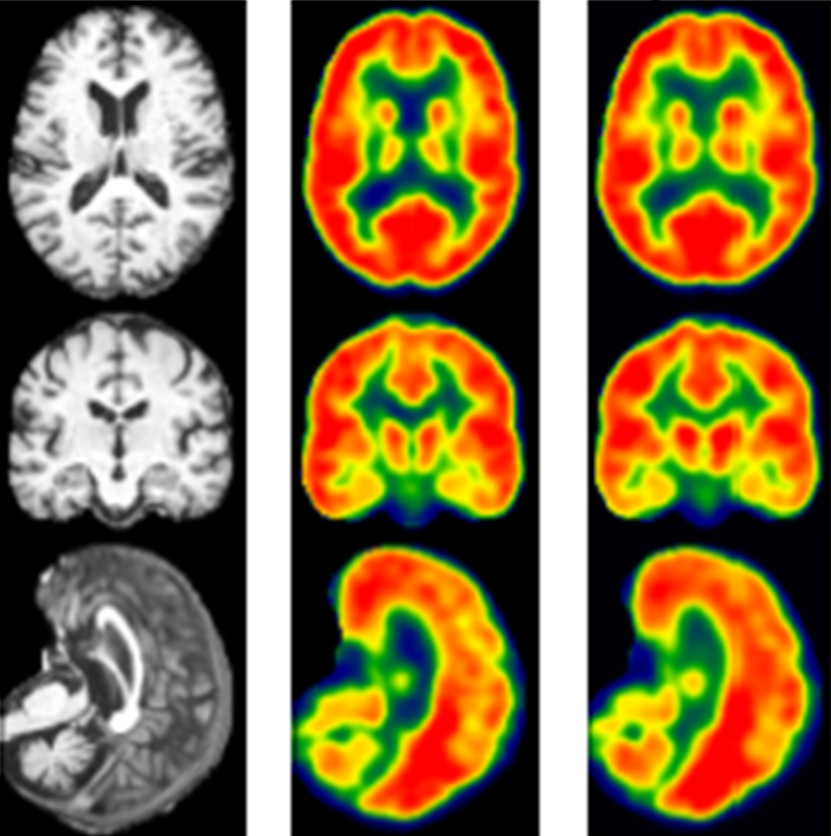

The Neuroimaging Research Core Lab is interested in utilizing multimodal imaging tools incorporating fMRI, DTI, perfusion imaging, cortical thinning, and other advanced MR imaging tools to explore various questions at the basic science, translational, and clinical levels.

The lab specializes in research on behavior, cognition and emotion; neurobiology of disease; development, plasticity and repair; and neuronal circuits.

Specifically, the lab combines neuroimaging measures such as functional magnetic resonance imaging (fMRI), diffusion tensor imaging (DTI), and other advanced neuroimaging as well as behavioral measures to identify prognostic factors that predict functional recovery, identify adaptive and maladaptive networks that contribute to functional recovery, and identify a critical time window for intervention in these patients. Our lab, in collaborations with Justin Williams’ Lab and TCNL, is developing Brain-Computer Interface (BCI) as well as cranial nerve noninvasive neuromodulation technologies as rehabilitation treatments for patients, which will lead to faster and more optimal levels of recovery.